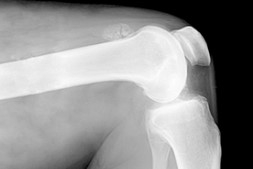

Больное колено нашего героя сможет излечить только высококвалифицированный хирург. Если хочешь попробовать себя в роли виртуального доктора, то начни играть в эту игру. Чрезмерная нагрузка на колени может провоцировать развитие серьезного заболевания. Во избежание этого молодой парень решил избавиться от проблемы, связанной с коленом. Вообще этот сустав очень хрупкий и поэтому чаще всего подвергается травмам, таким как переломы, трещины, смещения и прочее. Определить причину можно при помощи рентгена, потому и первое ваше действие - пройти рентген исследование.